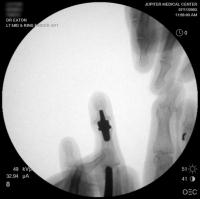

Intraoperative fluoroscopy using the same technique as above. The trial spacers:

Click for larger image

The final implant: